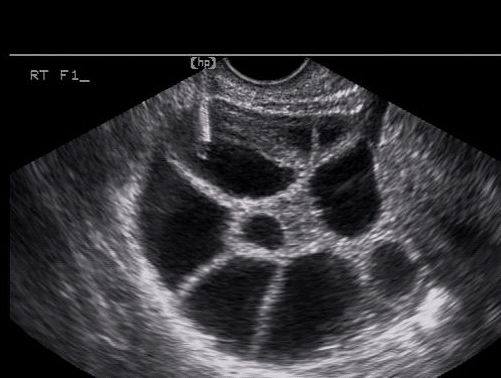

Q: 試管嬰兒治療,是否取到的卵數目越多成功率就越高?

這篇研究蒐集了15000個病人,皆為第一次接受試管嬰兒治療,分析其取卵數和累積活產率的關係。

研究的結論是「取卵數越多,累積活產率越高;當取卵數大於25個以上時,累積活產率可以高達70 %」

倘若只有考慮新鮮胚胎植入,那麼取卵數在7到20個之間,新鮮週期活產率是一樣的;若取卵數大於20個以上,新鮮週期的活產率就下降了,主要的原因是子宮著床環境變得不好,在此時就必須做兩段式試管嬰兒,也就是利用冷凍胚胎的植入來提高累積活產率。